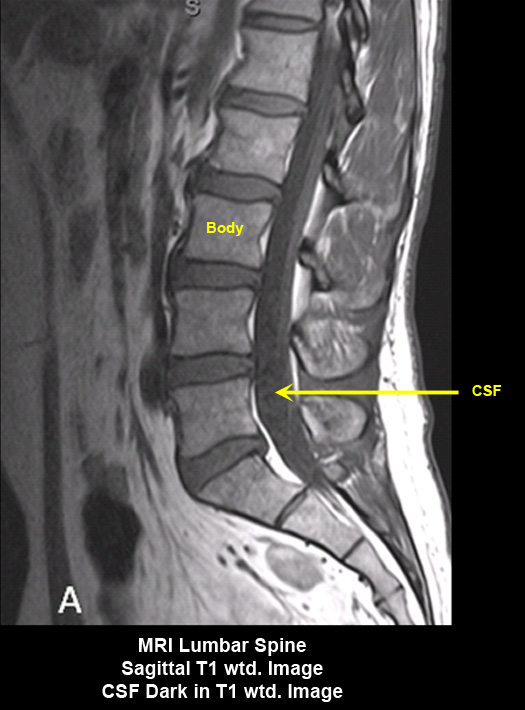

MR Brain and Spine